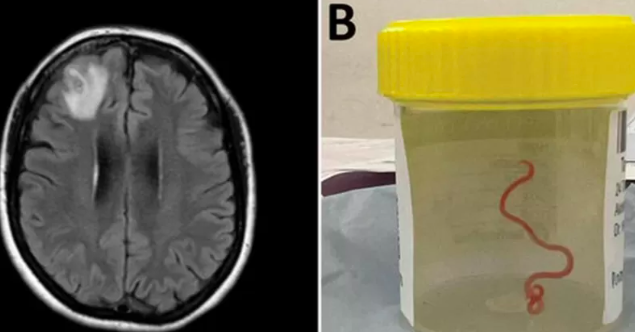

Una mujer australiana de 64 años se sometió a una operación cerebral sin saber que albergaba un parásito improbable pero peligroso. El neurocirujano Dr. Hari Priya Bandi encontró y extrajo de su cerebro un parásito vivo de ocho centímetros de longitud, el primero de este tipo registrado en la historia de la medicina humana.

La mujer ingresó en el hospital en 2021, tras semanas de dolor abdominal y diarrea, así como tos seca y fiebre. Un año después del diagnóstico aparecieron síntomas más específicos, como pérdida de memoria y depresión, por lo que los médicos pudieron confirmar la presencia de Ophidascaris robertsi en su organismo.